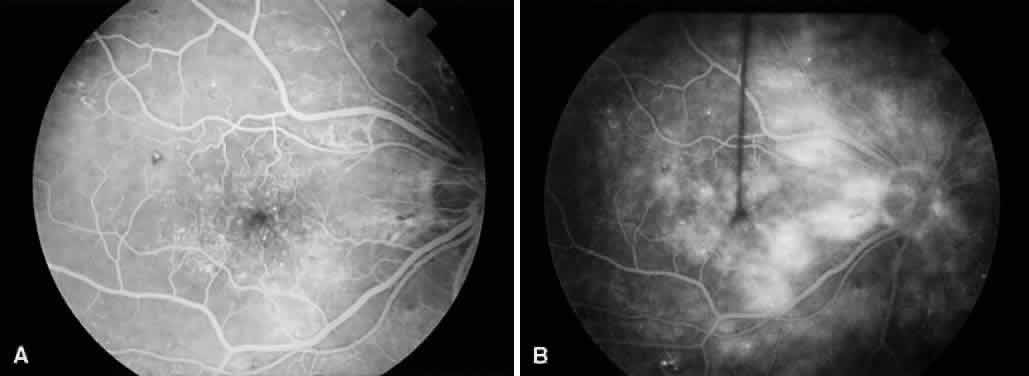

SILICONE OIL IN DIABETIC VITRECTOMY

Another controversial topic is the role of silicone oil in patients with diabetic retinopathy. Whereas some authors58,59 advocate using silicone oil in patients with severe PDR to promote stabilization or regression of iris neovascularization, others60 question its benefit in diabetic patients. Lean and associates were the first to use silicone oil with vitrectomy for severe PDR.61 Several others have since published series of patients where silicone oil was used for severe PDR.62–68 Many of these series involved eyes that had failed prior vitrectomy for PDR and had recurrent retinal detachment with proliferative vitreoretinopathy and iris neovascularization (Fig. 7). These eyes have a particularly poor prognosis and often lose all vision and progress to phthisis. For series that included only such eyes, anatomic success (total retinal reattachment) ranged from 30% to 70%, which may be higher than expected without silicone oil. Visual acuity results, however, remained disappointing. In addition, several complications of silicone oil were reported, including cataract formation, keratopathy, glaucoma, and redetachment secondary to reproliferation. Other reports have examined the use of silicone oil for recurrent vitreous hemorrhages after vitrectomy.37,69,70 Gabel and Beck report a series of 135 consecutive cases of pars plana vitrectomy for PDR where balanced salt solution was used in 69 eyes and silicone oil was used in 66 eyes as a vitreous substitute.71 Indications for use of silicone oil included the presence of several retinotomies or retinectomies, or sharply increased risk for rebleeding. Postoperatively, for eyes with a minimum of 6 months' follow-up (only 58 of 135 eyes), the two groups achieved similar functional results, with 18 of 23 eyes (78%) in the silicone oil group and 27 of 35 eyes (77%) in the balanced salt solution group achieving visual acuity greater than or equal to 0.02 (4/200). A worse functional outcome would be expected from the eyes where silicone oil was used because of a worse preoperative condition. Thus, these findings may indicate that silicone oil is useful in such eyes. However, no comparison was made to similar eyes treated with long-acting gas tamponade. Certain characteristics of silicone oil may be advantageous for eyes with PDR. Because of its optical qualities, earlier visual rehabilitation may be possible, and fundus details are clearly visible, permitting intraoperative and postoperative laser photocoagulation. Also, silicone oil, unlike gases, provides indefinite retinal tamponade. Experimental evidence in animal models suggests that silicone oil may inhibit iris neovascularization by compartmentalizing the eye and preventing anterior diffusion of vasoproliferative substances.57,72 However, clinical studies have been unable to confirm this because of the multiple variables that may lead to iris neovascularization. Oil emulsification and reproliferation may be more common in diabetics than in nondiabetic patients. If silicone oil is to be used in an aphakic or pseudophakic eye of a diabetic, it is important to create a large inferior iridectomy to prevent silicone oil from migrating anteriorly and contacting the cornea. Madreperla and McCuen showed that postoperative closure of the iridectomy occurs more frequently in diabetics than in nondiabetics, and closure of the iridectomy is highly correlated with anterior oil migration.73

Fig. 7. A. Preoperative fundus photograph of an eye with recurrent combined retinal detachment from proliferative diabetic retinopathy and proliferative vitreoretinopathy. B. Postoperative fundus photograph of the same eye. The retina has been successfully reattached using silicone oil tamponade.